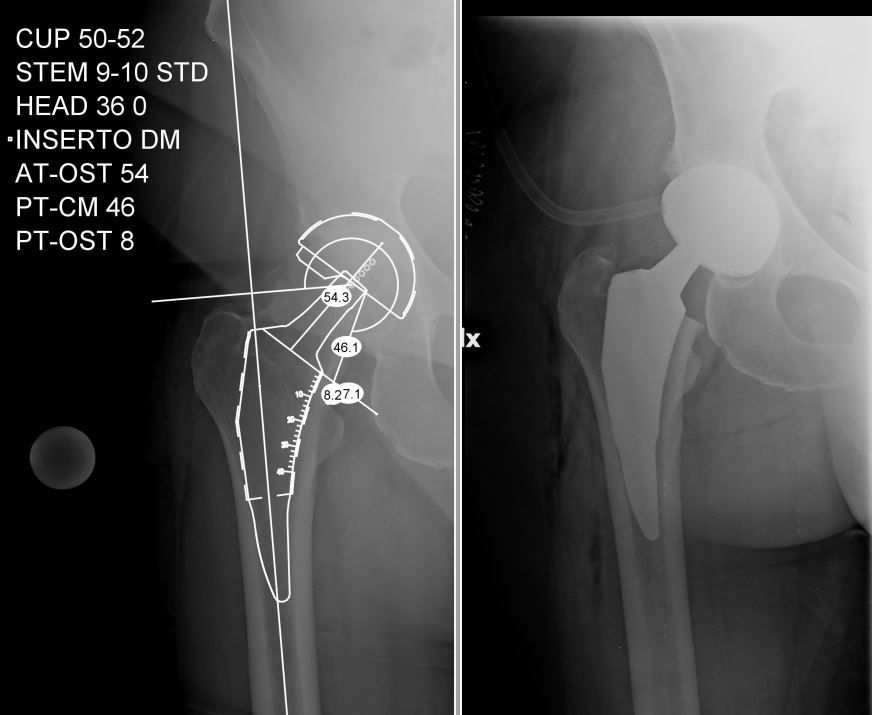

Il Dr. Giuntoli si è laureato in Medicina e Chirurgia nel 2014 presso l’Università degli Studi di Firenze e successivamente nel 2020, ha conseguito la Specializzazione in Ortopedia e Traumatologia presso l’Università degli Studi di Pisa con votazione di 110/110 e Lode, discutendo la tesi: “I sensori di pressione nella Protesi Totale di Ginocchio: confronto clinico e funzionale mediante Gait Analysis tra la tecnica convenzionale e il sistema VERASENSE”. Dal 2021 al 2024 ha svolto attività clinica, chirurgica ed universitaria presso la U.O. Ortopedia e Traumatologia I Universitaria dell'Azienda Ospedaliero Universitaria Pisana (AOUP) nell'Ospedale di Cisanello di Pisa Da gennaio 2023 svolge attività di docenza di ecografia muscoloscheletrica diagnostica e procedurale (infiltrativa) presso la scuola SIUMB di Pisa, di cui è anche docente dal 2024 presso l'Università di Pisa. Attualmente Dirigente Medico presso il CESAT (Centro Eccellenza Sostituzione Articolare Regione Toscana) - Ospedale San Pietro Igneo di Fucecchio, presso la quale svolge la maggior parte dell'attività clinica, chirurgica e di ricerca soprattutto nell'ambito della protesica di anca e ginocchio e dell'artroscopia di ginocchio. Da settembre 2023 svolge attività chirurgica anche presso la casa di cura privata San Rossore di Pisa e la casi di cura privata San Paolo di Pistoia. Istruzione e Formazione: • Laurea in Medicina e Chirurgia presso Università degli Studi di Firenze in data 28/10/14 • Specializzazione in Ortopedia e Traumatologia presso Università degli Studi di Pisa in data 17/11/20 • Il Dott. Michele Giuntoli ha partecipato a numerosi corsi di aggiornamento e perfezionamento in Italia e all'estero e collabora, attualmente, con le principali società scientifiche ortopediche nazionali ed internazionali • In qualità di relatore ha preso parte a diversi congressi e seminari ed è autore di diverse pubblicazioni scientifiche pubblicate su riviste del settore nazionali ed internazionali Dal 2015 al 2020 ha svolto attività di formazione c/o la Scuola di Specializzazione in Ortopedia e Traumatologia dell’Università degli Studi di Pisa (sotto la direzione del Prof. Lisanti e del Prof. Capanna effettuando attività clinica e chirurgica di Ortopedia e Traumatologia maggiore e minore in qualità di Specializzando presso le U.O. di Ortopedia e Traumatologia I (Dir. Prof. Scaglione) e II (Dir. Prof. Capanna) della medesima Università. Nel 2019 e nel 2020 ha frequentato in qualità di Specializzando la U.O. di Ortopedia e Traumatologia dell'Ospedale F. Lotti di Pontedera (Dir. F. Carnesecchi), dell'Ospedale Versilia di Lido di Camaiore (Dir. M. Manca) ed anche presso l'Ospedale di Livorno (Dir. A. Augusti), svolgendo prevalentemente attività chirurgica di Ortopedia e Traumatologia maggiore e minore. Nel 2018, in qualità di specializzando, ha effettuato una fellowship internazionale presso il Dipartimento di Chirurgia Ortopedica e Bio-ingegneria della Scuola di Medicina della Stanford University (Palo Alto, California, USA) svolgendo gran parte dell'attività di ricerca sulla chirurgia protesica di ginocchio al VA Health Care System di Palo Alto sotto la supervisione del Prof. Pier Francesco Indelli. Ha acquisito nell'anno 2021 competenze ecografiche per l'apparato muscolo-scheletrico ottenendo il diploma nazionale SIUMB. Premi e riconoscimenti: •Vincitore Borsa di Studio OTODI Young Conseguita presso il 50° Congresso Nazionale OTODI (Sorrento, 23-24 Maggio 2019) in data 24 maggio 2019 con la presentazione Elettronica “Protesi totale di ginocchio primaria total stabilizer: risultati clinici e strumentali a breve-medio termine” Pubblicazioni • https://www.researchgate.net/profile/Michele_Giuntoli • https://scholar.google.com/citations?hl=it&user=TY6iufsAAAAJ • https://pubmed.ncbi.nlm.nih.gov/?term=giuntoli%2C+michele%5BAuthor%5D&sort= Enti e società scientifiche: - SIOT (Società Italiana di Ortopedia e Traumatologia) - OTODI (Ortopedici Traumatologi Ospedalieri d'Italia) - ESSKA (European Society of Sports Traumatology, Knee Surgery and Arthroscopy) - EKA (European Knee Associates) - SIUMB (Società Italiana in Ultrasonologia in Medicina e Biologia). Abilitazione: • Ordini dei Medici Chirurghi e degli Odontoiatri (FNOMCEO) n. 2233 iscritto il 19/02/2015

• Chirurgia dell'anca

• Chirurgia protesica con robot